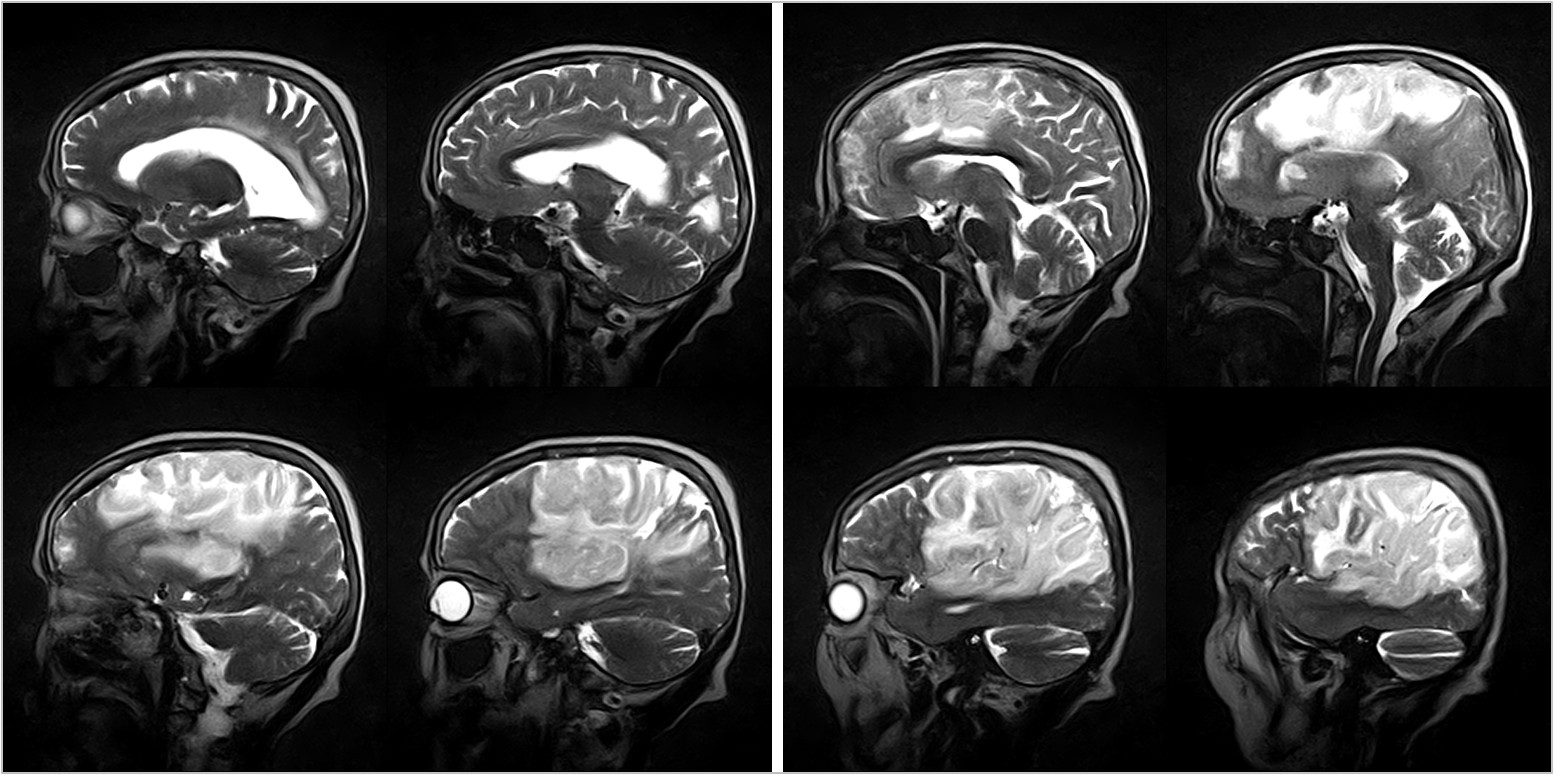

Hình ảnh lâm sàng